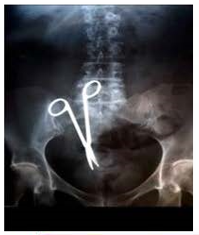

1. A patient with previous history of abdominal surgery comes to hospital with abdominal pain and fever. X-ray of abdomen is shown below. This corresponds to